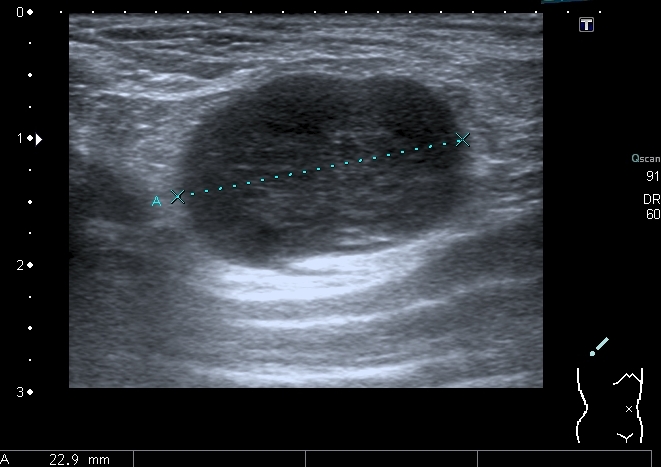

12-years old boy with torax palpable mass 5x3 cm.

Сегодня смотрел мальчика 12 лет, у которого на грудной клетке пальпируется опухоль около 5 см х3 см.

На УЗИ - такая картинка:

Деструкция корткального слоя 7-го ребра с ткаенвым компонетом, исходящим из кости. 7th rib destruction with solid mass

Поперечный скан. Transverse scan